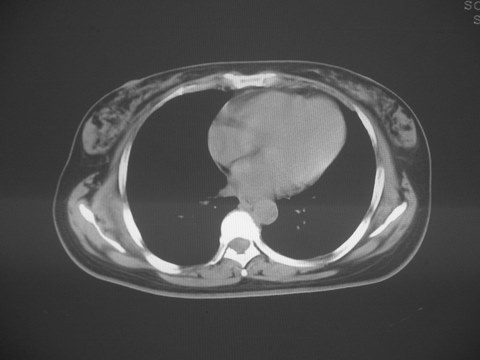

无意中发现右背部肩胛下缘半球状突起,无红,热,痛感觉。拍平片未见异常。ct发现右肩胛下角深层新月型软组织肿胀,ct值-50至15,大家看看是什么性质,来源,初步考虑来源于下后锯肿,考虑下后锯肌肿胀,可是病人无明确外伤史,也不疼痛

典型的弹性纤维瘤,从部位\\形态\\密度来看均极典型.现引用lzdyjg老师的点评:

一、弹性纤维瘤临床

是一种罕见的良性结缔组织病变,大多数学者认为是肩胛下角和胸壁之间的机械摩擦引起,是异常弹性组织发生的反应性的肿瘤样增生.82-99%的弹性纤维瘤位于肩胛骨下角附近的深部软组织内,也可发生于胸壁,肘部\\颈部\\髋部大腿\\足部\\坐骨结节\\股骨大转子附近.

三、弹性纤维瘤影像

典型位于背部,在肩胛下角和胸壁软组织之间,肿瘤表面为菱形肌和背阔肌所被覆深部,紧邻肋骨和肋间肌,呈半圆形或扁豆状,宽基底与胸壁相交,边界比较清楚,相邻的肌肉和肋骨无侵蚀,部分病变与其表面的临近肌肉之间可受压呈弧形的脂肪界面,肿瘤周围软组织无水肿。

从mr表现可以推断ct影像,即肿块呈软组织密度,病灶内可出现脂肪密度的低密度影。